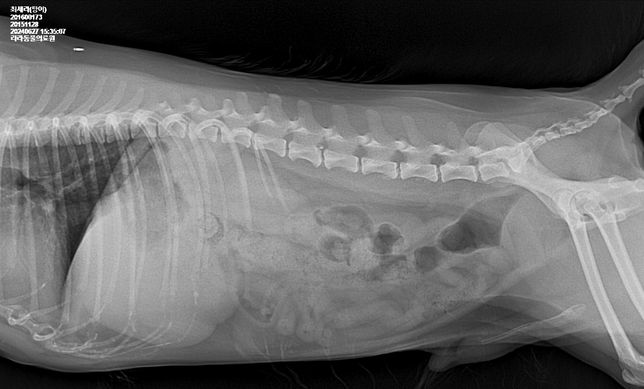

- 반려동물 건강반려동물Q. 강아지 몸속에 1.8cm물체가 있는것 같다는데 뭔지 모르겠어요건강검진 하면서 초음파를 찍었는데 강아지 몸속에 1.8cm 물체인지 뭔가가 보인다고 합니다 건강검진은 아무이상 없었구요의사선생님은 괜찮을것 같다고 했는데그리고나서 갈색토를 했구요 오늘아침에는 묽은변을 봤어요 (활력좋구요 사료먹는거 배변하는거는 이상없었습니다)자세한건 내시경을 해야한다고하네요..저것만봐서는 물체가 있는것같나요?엑스레이도 찍었는데 엑스레이로는 안보이는것같아요